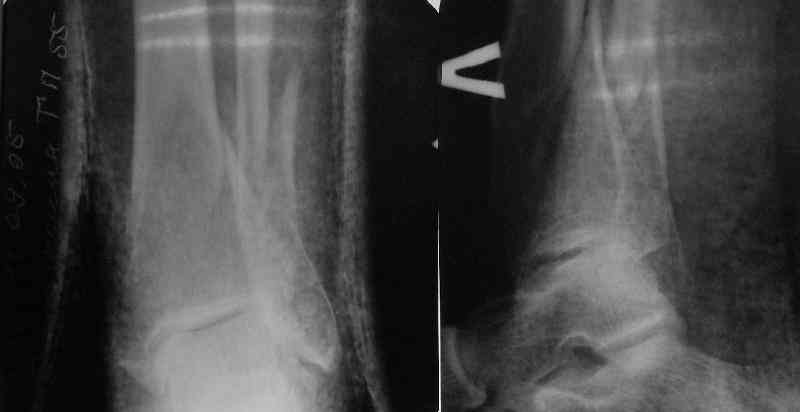

A typical case is attached, also an image with intra-op reduction obtained by a small wire distractor, in the moment of insertion a Poller wire in AP direction. Fixation by a SIGN nail. Despite the fibula was not fixed healing was obtained with the unchanged alignment.

Very interesting application, but is the final position in a little distal varus with some fibula

distraction? Would that have been eliminated by fibula plating?

At least both the ankle mortise and tibial alignment look acceptable, don't they?

I am just trying to illustrate that prevention of 1)tibial valgus and 2)loss of reduction can be provided without fibular plating. Small changes of conventional nailing techniques allow to maintain reduction of the tibia reliably without adjunctive fibular stabilization.

In delayed cases acute length restoration performed only in the tibia may leave the fibula shortened thus change the mortise. So it is reasonable to restore length of both bones simultaneously by distractor and fix the fibula not with open reduction and plating but just by a single perQ screw. Example attached.